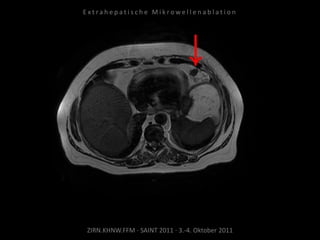

Ausgangsbildgebung:

MRT vom 19.01.2010

Bildgebung vor MWA:

MRT 03.02.2010

Situation:

Bei Z.n. Prostataresektion + Radiatio

+ Seed nun Rezidiv in kritischer

Position.